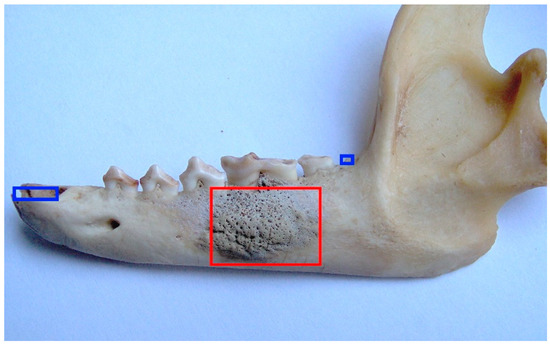

Enamel hypoplasia was not detected in the female raccoon dog skulls examined in this study. Regarding periapical lesions, only one case was identified (ID M–578; Figure 10). In the mandible, the bone tissue around the M1 was strongly affected, and resulted in porosity.

Figure 10.

ID M–578, female. Approx. length—90 mm. Left-mandible porous bone tissue around the M1 (marked in red rectangle). Note: blue squares mark the artefactual tooth loss.